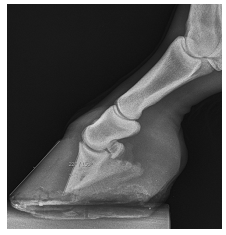

Caso Clínico: Égua Mangalarga Marchador, de 8 anos, com claudicação Grau V nos membros torácicos, sem conseguir retirar o membro direito do solo, com sensibilidade exacerbada na sola. O quadro surgiu após prova de vaquejada há cerca de 4 meses. No raio-X, a imagem do membro torácico esquerdo evidenciou laminite crônica (rotação de falange distal maior que 15º), conforme imagem abaixo.

I. Uma das alternativas terapêuticas é a tenotomia do flexor digital superficial.

II. Rotações de falange distal entre 15 a 20º, se bem cuidadas, têm prognóstico bom e retorno do equino à carreira atlética.

III. Se houver perfuração de sola, uma das alternativas para combater a osteomielite é o fresamento da terceira falange.